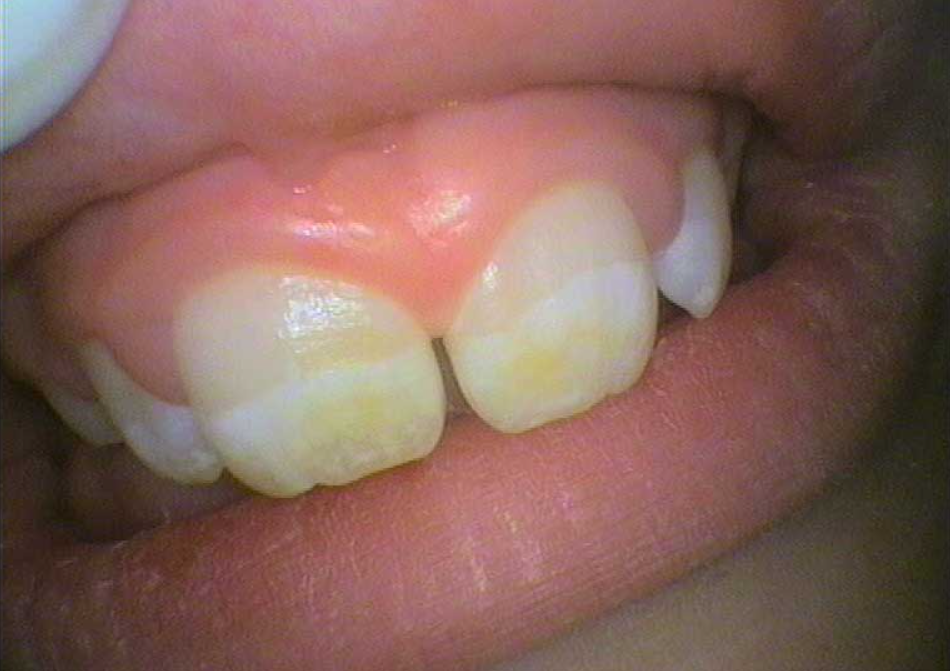

礦物質沉積-牙齒鈣化(圖片來源:Enamel defects (Hypoplasia and Hypo-calcification))

- 鈣化通常是牙齒表面沉積較硬的鈣化斑塊,顏色可偏白或偏黃。

- 多與飲食、口水礦物質含量或舊牙菌斑鈣化(初期牙結石)有關。

- 顯現為亮面白斑,而非霧面,通常不具「蛀牙活性」。

- 仍需清潔與追蹤,但不等於牙齒正在被蛀蝕。